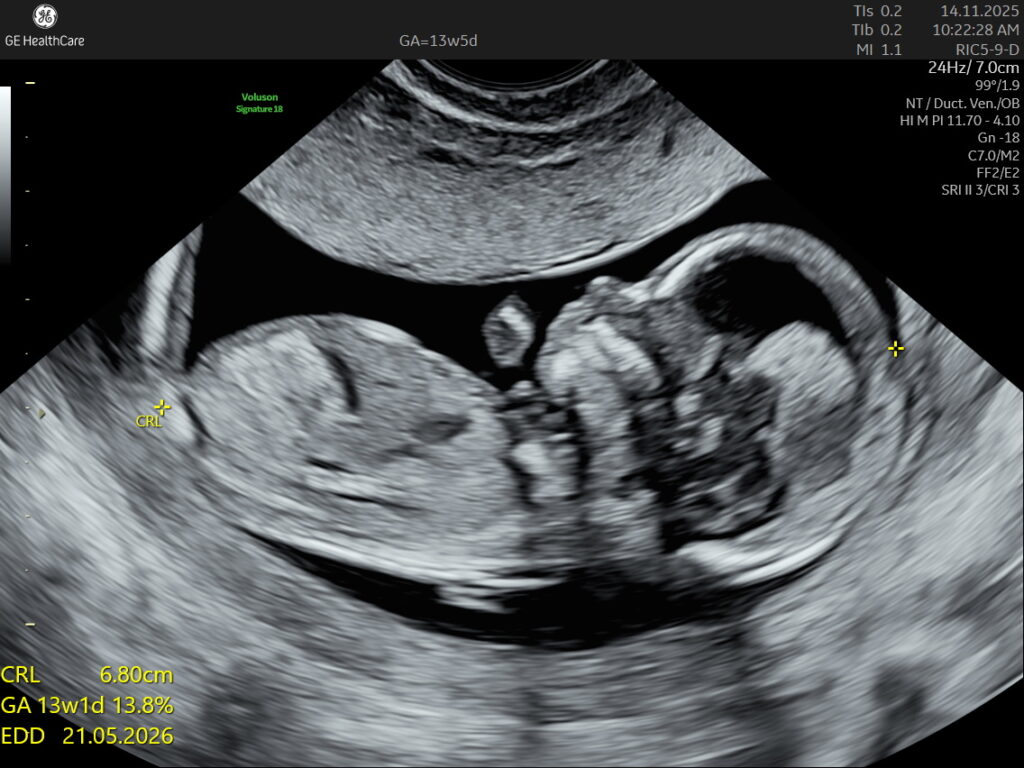

Fetal NT Scan (12-13 weeks GA)

Nuchal Translucency Scan at NESA Institute of Fetal Medicine, Kolkata Looking for a reliable Fetal NT (Nuchal Translucency) Scan centre

Precision Diagnostics powered by state-of-the-art GE Voluson systems designed for women and prenatal care.